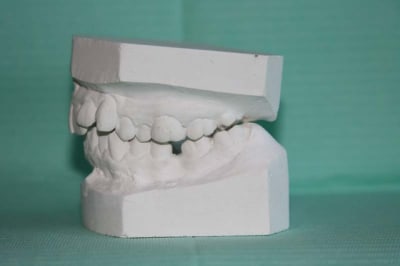

MOULAGES

Moulage 3 kvumyd - Eugenol

Moulage 1 vlrapq - Eugenol

Moulage 2 dllhb9 - Eugenol

Moulage 4 etnevt - Eugenol